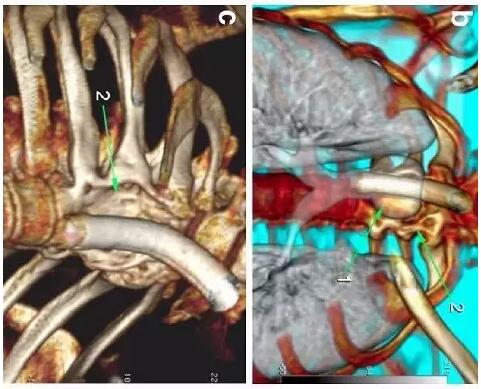

胸部CT顯示氣切套管氣囊周圍氣管擴(kuò)張,胸1-4椎體前部受到侵蝕(下圖a-c)。

下圖箭頭1為氣切套管氣囊緊貼T1-4椎體水平,造成椎體前部受到侵蝕(箭頭2):

作者推測患者骨質(zhì)吸收、骨髓炎與氣切套管氣囊過度膨脹有關(guān),為氣囊過度膨脹造成椎體血流灌注降低所致。在我院住院期間,我們也發(fā)現(xiàn)高氣囊壓力才能防止漏氣。經(jīng)食道內(nèi)鏡檢查未發(fā)現(xiàn)氣管食管瘺。